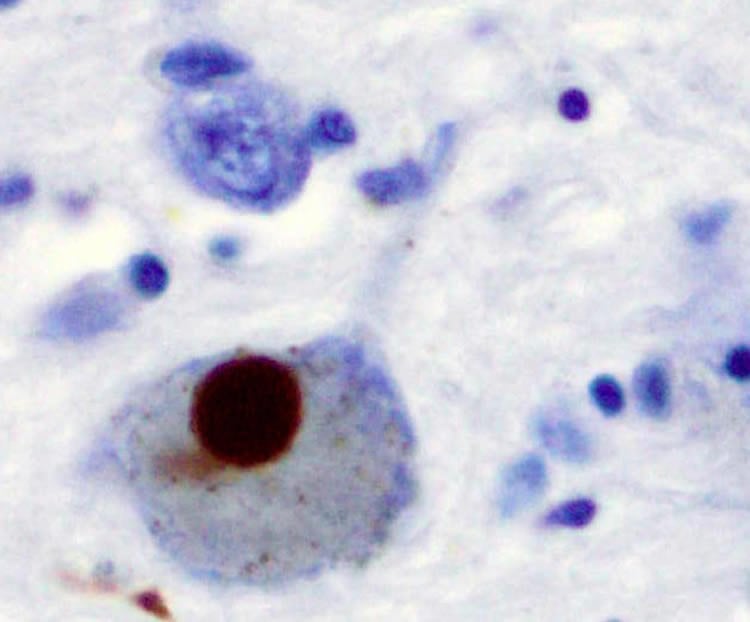

This image shows positive α-Synuclein staining of a Lewy body in a patient with Parkinson's disease.

FeaturedNeurology

·September 29, 2014·2 min read

A “Frenemy” in Parkinson’s Disease Takes to Crowdsourcing

A protein associated with Parkinson's disease regulates neurotransmission by self association, a new study reports.